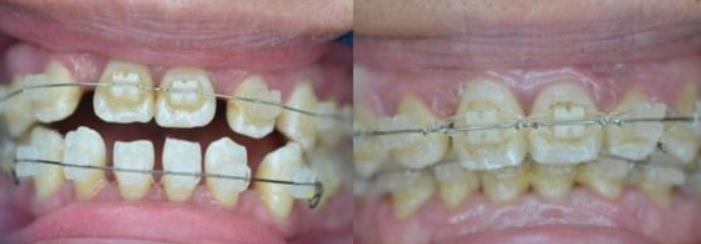

牙齒矯正半個(gè)月

后來(lái)我才知道牙齒不舒服的感覺,是因?yàn)檠例X在進(jìn)行重新排列。帶上牙套進(jìn)行矯正的半個(gè)月之后,我發(fā)現(xiàn)我的牙齒變得緊密了很多,而且跟別人說(shuō)話也沒有那種大舌頭的感覺了。就是每次吃飯的時(shí)候需要吧牙套拿下來(lái),這個(gè)過(guò)程有些麻煩,其他的都可以接受。